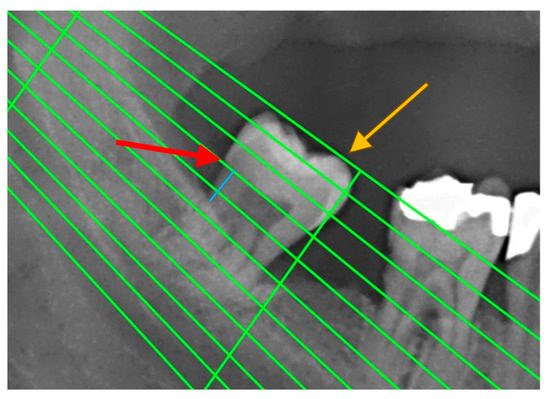

Periodontal disease was also confirmed by measuring radiographic bone loss (RBL) on dental panoramic tomograms (DPTs). All DPTs were taken using an Orthophos XG 3D device (Sirona Dental Systems GmbH, Bensheim, Germany) in the Department of Dentistry at the Faculty of Medical Sciences, University of Kragujevac. To clarify alveolar bone levels and root apices of the entire dentition, all radiographic images were enhanced in the picture editing software GIMP (GNU Image Manipulation Program, Software version 2.10) and were subsequently printed and used for measuring the distance [22] (Figure 1). Periodontal disease staging was assessed from the classification of 2018 [19,23] with extracted referent values by stages (Table 1).

Figure 1. An example of measuring radiographic bone loss using a Schei ruler, where the red arrow indicates the line tangent to the cementoenamel junction, the yellow arrow indicates the line tangent to the highest point of the crown, and the blue line represents approximately 1.5 fields between the cementoenamel junction and the alveolar bone level.